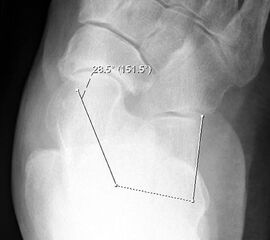

Konventionelles Röntgen

Stehende Aufnahmen des Fußes dorsoplantar (dp) und seitlich sowie des OSG anteroposterior (ap) sind die Grundlage der konventionellen Röntgendiagnostik (Abb. 5). Ergänzend werden gelegentlich die Rückfuβ-Alignement Aufnahme nach Saltzman 19 und Vergleichsaufnahmen der Gegenseite durchgeführt.

Der Talo-Metatarsale I Winkel bzw. die laterale talonaviculare Subluxation auf der stehenden dorsoplantaren Aufnahme des Fuβes dokumentieren das Ausmaβ des Vorfuβ abductus (Abb. 6 a,b). Ein dp Talo-Metatarsale I Winkel von > 10° (nach medial konvex) ist als pathologisch anzusehen. Mit der Bestimmung der talocalcanearen Divergenz (Abb. 6 c) erhält man ein Eindruck über das Ausmaβ des Rückfuβ valgus; eine leichte Divergenz bis ca. 12° gilt als physiologisch 20.

Auf der seitlichen, stehenden Aufnahme des Fußes wird ebenfalls der laterale Talo-Metatarsale I Winkel (Abb. 6 d) gemessen und so das kollabierte mediale Längsgewölbe dokumentiert. Auch hier gilt ein Talo-Metatarsale I Winkel von > 5° (nach plantar konvex) als pathologisch 21. Der Kollaps findet dabei meist im Talonaviculargelenk, seltener in der Naviculocuneiform-Gelenkreihe statt. Instabilität und Arthrose im 1. TMT sollten ausgeschlossen oder bei der Operationsplanung mit einbezogen werden. Weitere wichtige radiologische Messungen zur Beurteilung der Planovalgus-Statik und Progression der Deformität sind der laterale talo-calcaneare Winkel (Abb. 6 e) und der Abstand des Os cuneiforme-Unterrandes zum Untergrund (Abb. 6 f, Cuneiform height, 22. Eine anteriore Translation des Talus auf dem Kalkaneus findet man sowohl auf der ap, als auch auf der seitlichen Aufnahme des Fuβes mit Aufhebung der Cima-Linie.